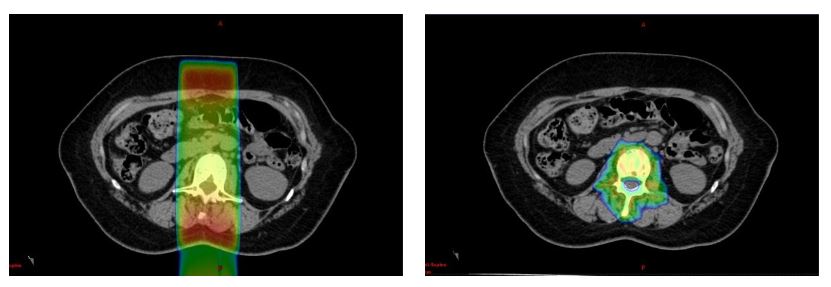

이 화상도 조금 전과 같은 통상 조사(왼쪽)와 IMRT(오른쪽)로 비교한 것입니다.

원전발암는 제거했지만 시간이 지나고 척추로 전이가 한 군데만 재발한 상황입니다. 사실 분류적으로는 정위 조사라는 장르지만, 기술적으로는 IMRT와 같은 방법으로 이루어지고 있습니다.

IMRT 쪽은 선량 분포의 가운데가 활짝 열려 있는 것이 보입니까? 여기는 척수라는 부분으로, 방사선이 너무조사하여 장애가 발생하면 하반신 마비 등이 일어나 버리는 부분입니다. 우리로서는 무슨 일이 있어도 장애를 남기고 싶지 않은 부분입니다. 기존의 통상 조사로는 이곳을 피하는 것이 불가능했습니다. 따라서 척추 병변에 대한 조사는 적당한 선량으로 억제하는 것이 주류였지만, 그렇게 되면 병변을 제어할 수 없는 경우도 많았습니다. IMRT 기술을 사용함으로써 전립선암과 마찬가지로 위험 장기의 선량을 억제하면서 투여선량을 증가시키고 병변 제어율을 향상시킬 수 있게 되었습니다.